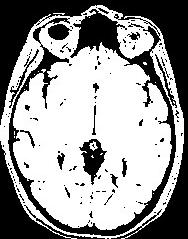

This procedure relies on the fact that the brain is a light and massive object surrounded by a black strip related to the skull, which largely isolates it from the other tissues. The image analysis procedure aims at splitting the few connexions between the brain and the external world using an erosion process very similar to geological phenomena or to the action of the rust, when it weakens metallic objects at the level of their bottlenecks before breaking them.

The grey level image is thresholded first in order to get a binary object (white on black background). During a second stage, an erosion process is simulated in order to trim the object until a given thickness. This erosion fathers several disconnected pieces. The largest one is selected as a seed of the brain. A dilation process makes the seed growth in order to recover the actual brain shape.

An illustration of the process at the level of a slice: